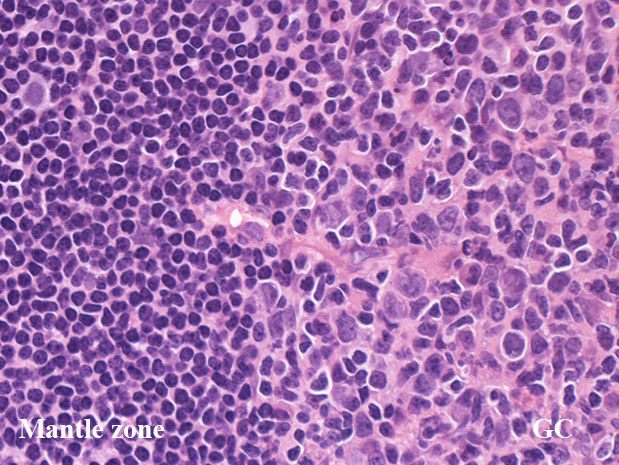

GC01.jpg

リンパ節の皮質cortexは, primary follicle(一次濾胞)とsecondary follicle(二次濾胞; 右図)から構成される.

secondary follicle;

胚中心(germinal center: GC)とmantle zoneをもつ.

mantle zoneはprimary follicle構成細胞と同じB細胞からなる. mantle zoneには厚い薄いがみられ, 薄いときはmantle zoneがないように見え, 子供のリンパ節に多い.

germinal center(GC)は, B細胞, T細胞, 抗原提示細胞, tindible-body macrophageが混在して構成されている. B細胞が優位に多く, small/ large cleaved cell(centrocytes)とlarge non-cleaved cells(centroblasts)が認められる。

正常胚中心のcentrocyte, centroblastsはbcl-2陰性であり, CD10, bcl-6が陽性となる. surface Igは低レベルであるが細胞質に通常 μ重鎖タイプ(IgM)Igが認められる.

T細胞はCD4+/ CD8-のhelper/inducer cellsであり, follicular (helper)T-cell:Tfhとよばれる. PD-1+, CXCL13+, CD57+.

高度に活性化された胚中心では, centrocyteとT細胞から構成される light zone (LZ)と増殖の盛んなcentroblastsとtindible-body macrophageの多いdark zone(DZ)が区分されるようになり, 極性(polarization)をもつといわれる.

centrocytes(左図), centroblasts(中央, 赤矢印), Mantle zone-GC boder(右図) クリックで拡大図.

centrocyteはくびれや切れ込みのある核をもつ中から大型の細胞で核小体は明瞭なものと不明瞭なものがある.

centroblastは類円形大型のvesicularな核をもったN/C比大の細胞. 核小体が複数個核辺縁にくっつくように認められる.

胚中心には核分裂像やapoptosis像が多く, 正常胚中心のMIB-1 indexは高い。(FLでは low MIB-1 indexとなる. 後述)